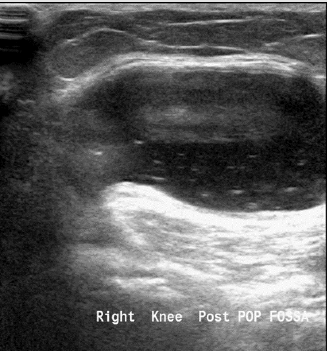

Figure 6: Baker’s cyst - located in the popliteal fossa between the tendon of the semimembranosus and the medial gastrocnemius. It’s size ranges from few millimeters to few centimeters, and it is a common reason for knee complaints, it can cause pain, or it might be asymptomatic. It also can be in relation to intraarticular effusion from mechanical or inflammatory aetiologies.